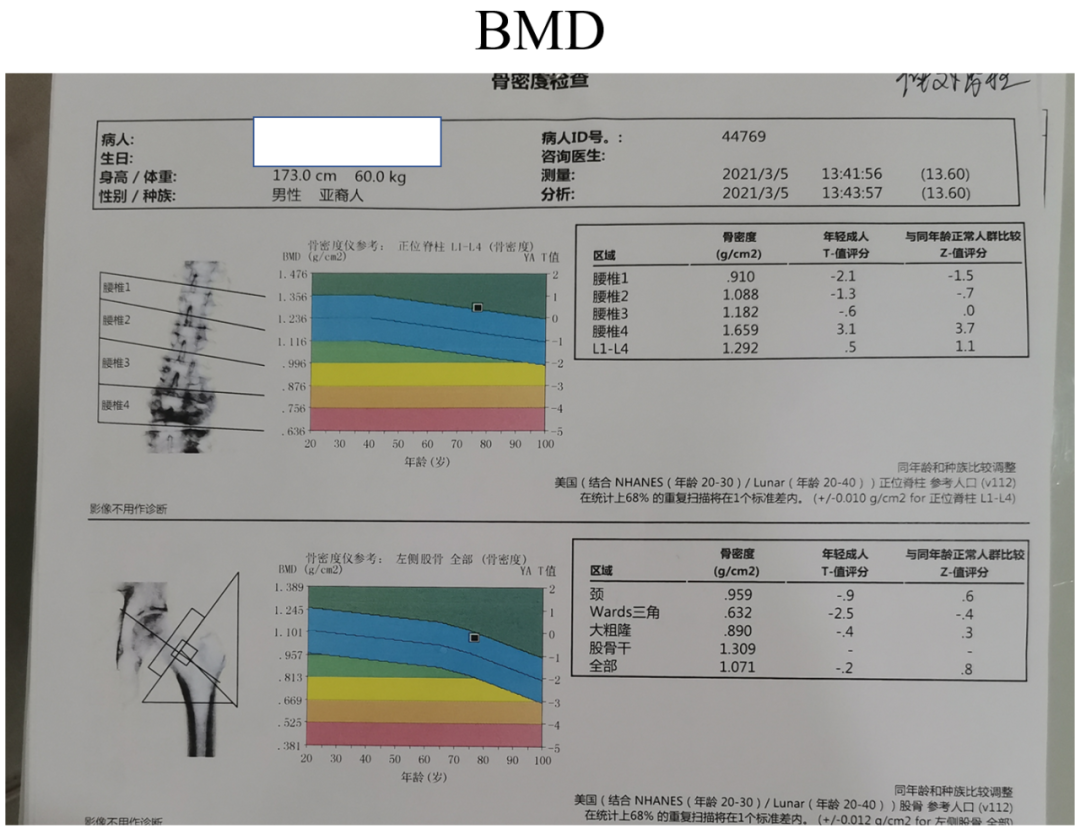

讨论主题:L4压缩骨折伴脊柱侧后凸畸形

男,76岁

影像资料:

腰椎侧后凸畸形

腰椎陈旧性压缩性骨折(L4)